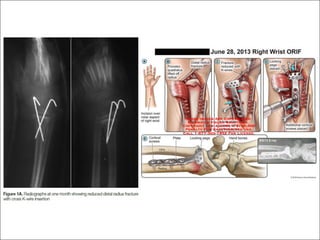

Reduction

DER	Parameters

Radial	inclinationVolar	tilt Radial	height

Indication for surgery

• Open fracture

• Unacceptable alignment

• Unstable

• Fernandez type II, IV, V and some case in I, III